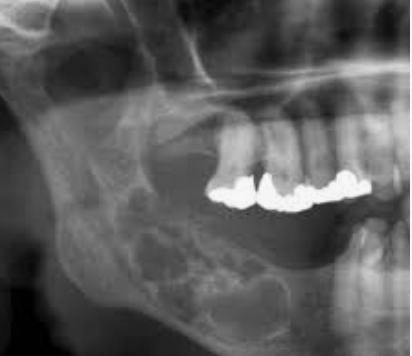

How does a keratocyst appear radiographically?

• Well defined

• Often multilocular radiolucent lesion with a corticated sharply demarcated bony wall which may extend from the angle of the mandible to the body and/or upwards into the ramus